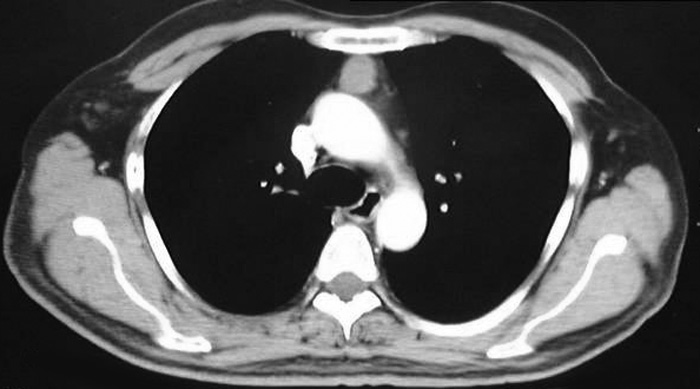

VATS thymectomy for thymoma is generally confined to small intrathymic and encapsulated tumours (Figures 11 and 12, Video 5) as there are oncological concerns of possible breach of the tumour capsule with the risk of tumour seeding. When performing VATS thymomectomy a modified no touch technique is used to minimize the risk of capsular breakage and tumour seeding, which are:

a.Only well encapsulated tumours screened on CT scan thorax are ideal for VATS.

Larger well-encapsulated tumours, preferably less than 5cm, are also suitable for VATS provided the above surgical oncological principles are strictly adhered to (Figures 13 and 14, Video 6). Minimally invasive thymomas are tumours detected to have limited invasion of a segment of lung, pleura, phrenic nerve or pericardium at the time of VATS. The above described oncological principles are adopted here where the non-tumorous part of the gland is mobilized first followed by en bloc removal of tumour together with a cuff of involved pericardium, lung or phrenic nerve. In invasive thymomas division of the involved phrenic nerve and a wedge of lung are carried out early so it can be used for traction and grasping when dissecting the tumor last. This is done by creating a passage between the lung (usually the anterior segment of upper lobe) and tumour. An endostapler is then introduced through the 10mm port and the involved lung is wedged by passing the stapler through the created passage. The tumor is always dissected last, especially if it invades the pericardium, because on opening the pericardium the pulsating heart makes subsequent dissection of the gland and tumor difficult and hazardous (Video 7). Dissecting the tumor last also minimizes tumor handling and manipulation. If the tumor is dissected first, its weight will obstruct the surgical field, making subsequent dissection of the rest of the gland difficult and oncologically hazardous (Video 8).